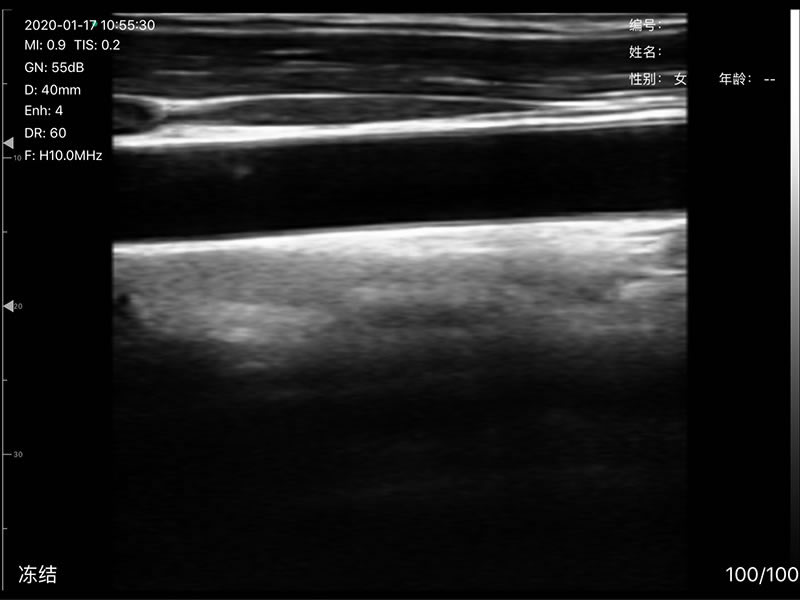

• 探头频率:相控阵2.2/3.6MHz,线阵7.5/10 MHz

• 扫描深度:相控阵20-240mm,线阵 20-100mm,可调